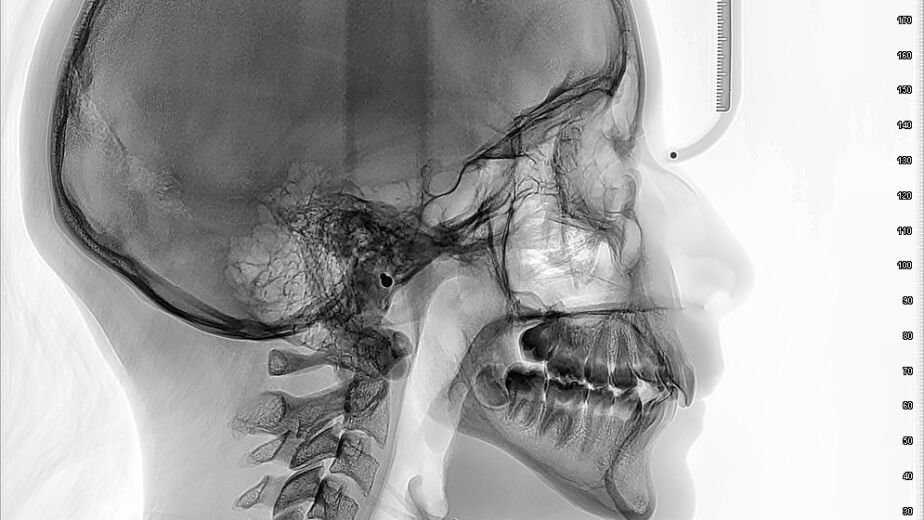

Un examen de tomografía axial computarizada (TAC) cervical es una herramienta de diagnóstico por imagen que permite a los médicos visualizar las estructuras óseas y los tejidos blandos del cuello. Este procedimiento utiliza una serie de rayos X tomados desde diferentes ángulos y los combina con tecnología informática para crear imágenes transversales detalladas.

Un TAC cervical, también conocido como tomografía computarizada de cuello, produce imágenes detalladas de la médula espinal, las vértebras cervicales (los huesos del cuello), los nervios, los vasos sanguíneos y otros tejidos blandos de la zona. Se diferencia de una radiografía tradicional en su capacidad para mostrar secciones transversales, lo que ofrece una perspectiva tridimensional del interior del cuerpo. Piense en ello como cortar un pan por la mitad para ver su interior, en lugar de solo verlo desde fuera.

Se le pedirá que se quite joyas, gafas, dentaduras postizas, audífonos, horquillas, pasadores o cualquier objeto metálico que pueda interferir con las imágenes. Es mejor usar ropa cómoda y holgada que no tenga cremalleras, botones o adornos metálicos. Considere que el metal aparecerá como un brillo en las imágenes, como una vela que interfiere con una fotografía, lo que podría ocultar estructuras importantes.